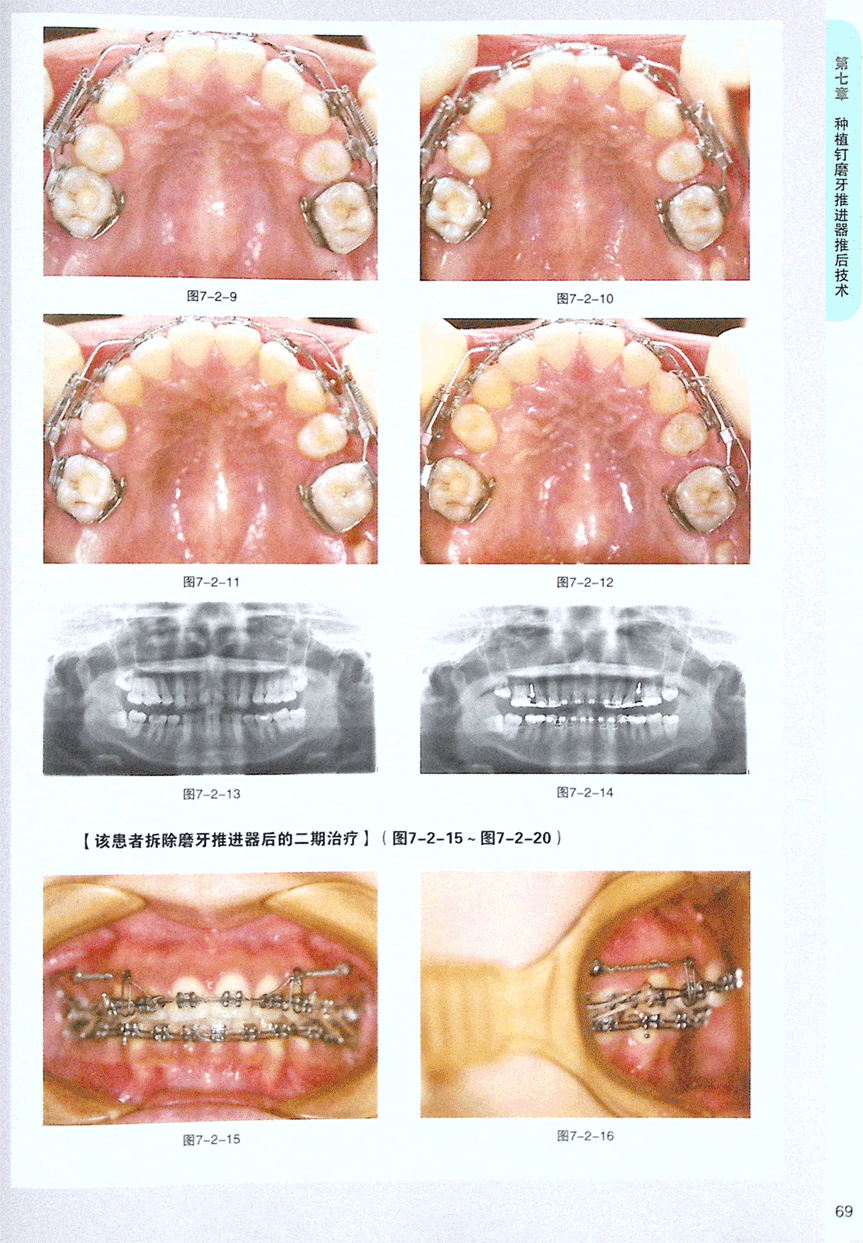

第二节 种植钉磨牙推进器推后技术